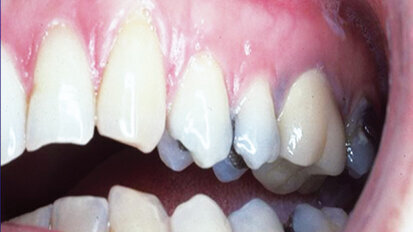

Complete reconstruction for a patient with chronic tooth decay

When oral health is neglected for extensive periods of time, dental conditions like tooth decay and periodontal disease can advance to a point that, prior ...